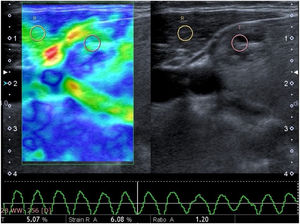

A routine B-mode ultrasound evaluation was obtained by having patients positioned on their backs with their necks slightly extended. B-mode ultrasonographic nodule features, such as size and side location (e.g., right, left), were recorded. SE was performed with a conventional ultrasound probe during a single US examination session using software connected to the machine. The probe was positioned perpendicular to the skin when pressure was applied, and lateral movement was avoided. The great cervical vessels were also avoided as much as possible. Additionally, strong initial compression was avoided due to the possibility of increasing the probability of false negative results. Patients were asked to hold their breath and not swallow during the examination in order to minimize the movement of the thyroid gland. After approximately seven to eight compression–relaxation cycles, the elastographic examinations were finalized. SR value measurements were obtained from appropriate relaxation waves on the velocity profile, and the SR was automatically calculated by the software. Each nodule was assessed based on different static images at least three times, with the mean value recorded as the final result. The radiologist performed the examination and evaluation for approximately 5–7 min for each patient. For the SR, the radiologist selected the rounded Region-Of-Interest (ROI), including the thyroid nodule and surrounding normal thyroid tissue or the ipsolateral Sternocleidomastoid Muscle (SCM), as a reference in order to provide a semi-quantitative analysis. The elastography score was also measured via the same method and determined by a color scale, ranging from green (i.e., softest components) to blue (i.e., hardest components). According to this assessment system, softer lesions are assigned lower elastography scores, while stiffer lesions are assigned higher elastography scores. The gray-scale images on the right and images of the strain elastogram on the left were displayed on the same screen for both methods (Figs. 1‒2).

Image of a 38 year-old woman from a dual screen US elastogram. The nodule exhibits a small degree of stiffness with a mixed color of mostly green, a little blue areas consistent with a score of 2. The strain ratio was 1.20. These results indicated a benign form of the disease, and histopathology confirmed a benign nodule.